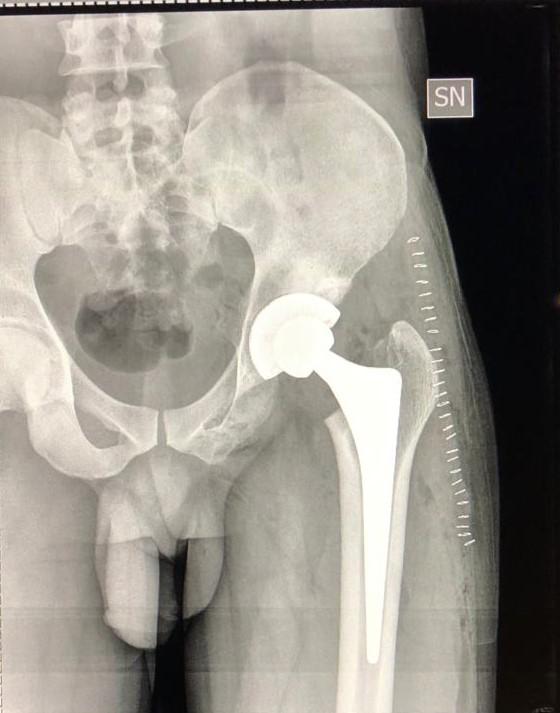

consiste nel ricostruire chirurgicamente l’articolazione formata dalla testa del femore e dall’acetabolo, mediante posizionamento di componenti protesiche, di cui quella acetabolare può essere rivestita con elemento in polietilene o ceramica.

Gli scopi della protesi dell’anca sono di rimuovere il dolore e fornire un’articolazione dotata di buona motilità e di stabilità.

La protesi totale d'anca è composta da 2 principali componenti che si articolano tra di loro e fissate “a pressione” o con un apposito cemento all'osso del paziente. La coppa acetabolare è un’emisfera che viene ancorata a pressione dentro l'acetabolo opportunamente preparato per accoglierla e che a sua volta contiene una coppetta in materiale plastico (polietilene) o ceramica che si articolerà perfettamente con la testa della protesi (metallo o ceramica) sostenuta dalla seconda componente, lo stelo femorale, fissato a pressione o “cementato” dentro al femore. L’intervento chirurgico è eseguito preferibilmente in anestesia locoregionale, mediante una incisione minima dei tessuti, in corrispondenza dell’estremità superiore della coscia (anteriormente o posteriormente, a seconda dell’accesso) e consiste nella rimozione della testa femorale e sostituzione dell’anca malata con applicazione di componenti protesiche. Il tipo di anestesia più indicata nel Suo caso, tuttavia, sarà scelto dall’anestesista, che Le darà tutte le informazioni utili in merito.

Presso il nostro centro la scelta dell’impianto da parte del chirurgo, avviene prima dell’intervento nella fase di planning – pianificazione e si basa su diversi fattori, primo tra tutti le condizioni locali dell’osso. Vengono utilizzati dei software che permettono di calcolare con precisione il tipo di impianto protesico che più si adatta alle caratteristiche del paziente per poter riprodurre la normale anatomia dell’anca.

ARTROSI DELLANCA2   ARTROSI DELLANCA 3